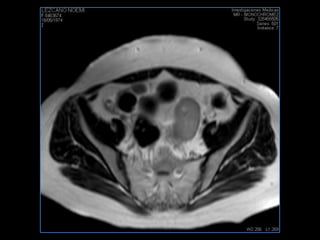

PROTOCOLO pelvis SAG T2, Y FAT SAT (FINOS) AXIAL T1  AX FAT SAT CON   GADOLINIO :  AX T1 Y COR T1 SAT: NO  FASE: RL THK: 3MM  COIL:  GAP: (FACTOR 1.4) 1MM FOV: 40 CM NEX:2 SINCRONIZACION RESPIRATORIA EN 3 O 4 CICLOS ALE